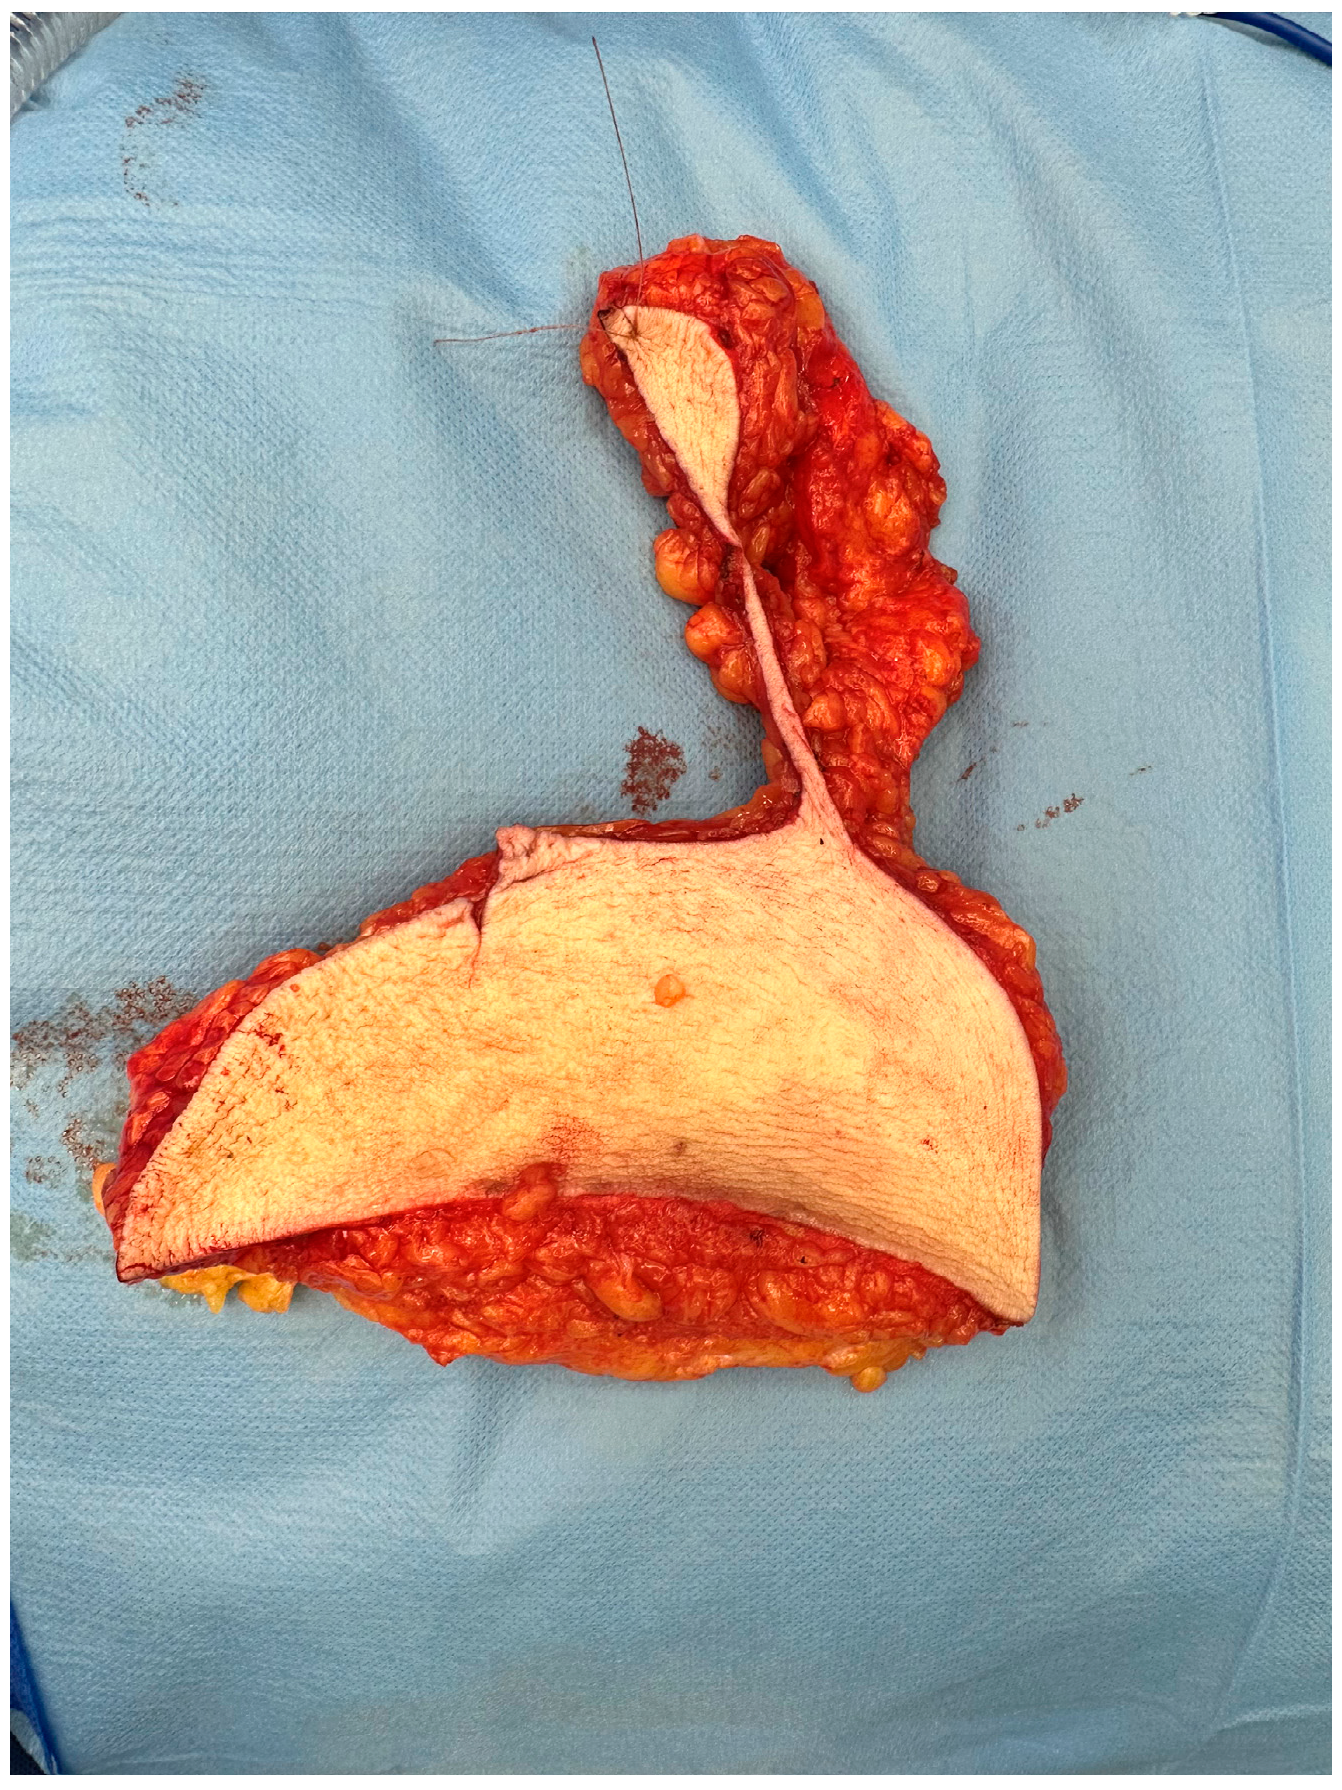

2.2. Surgical Technique

All patients underwent contralateral breast reduction surgery for symmetry using the Wise pattern technique. This is the most common technique used in breast reduction surgery [8]. The surgical protocol was changed on 20 July 2022 as resections were made in toto and marking of the excised tissue was conducted cranially (Figure 1). This consensus started since that date and all the plastic surgeons involved in this procedure followed it accordingly. Before this protocol, the resection of the breast tissue could be conducted in toto or in small pieces, and no marking was requested.

Figure 1. Reduction specimen marked cranially.